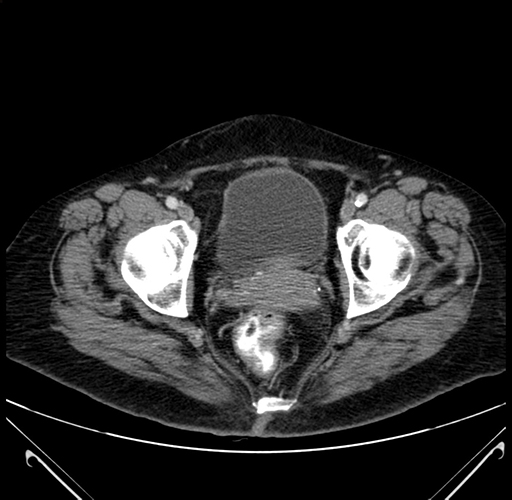

Pre-Chemo: Axial Venous

Axial Venous